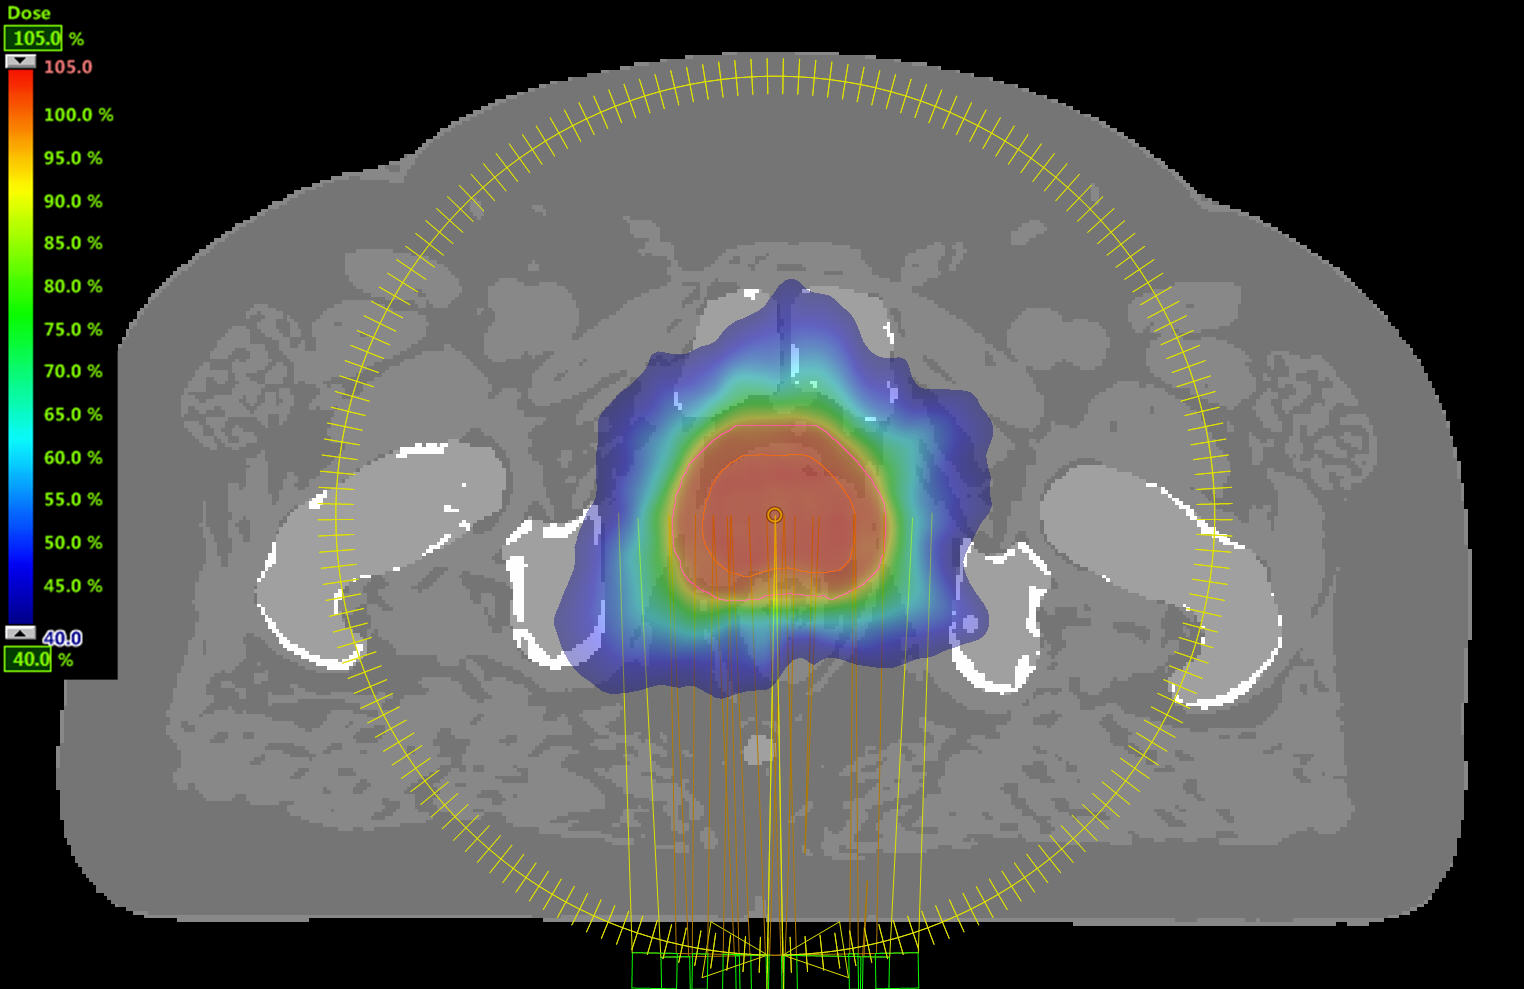

77-year-old male with prostate cancer cT3aN0M0, Gleason 8 and PSA 52 µg/L referred to androgen deprivation and radiation therapy with a prescribed dose of 50 Gy to the pelvic lymph node regions and 76 Gy to the prostate. Patient underwent MRI on Ingenia MR-RT 1.5T using FlexCoverage Anterior Coil in combination with the integrated Posterior Coil. Dose planning was performed on MRI imaging data.